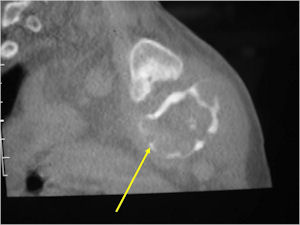

- The periosteum remains intact around the soft tissue component. Might need a CT scan to detect the subtle calcification (Egg Shell Rim of Calcification) associated with an intact periosteal reaction

- The lesion may be entirely radiolucent but usually shows some degree of mineralization. Mineralization may appear stippled like cartilage but do not see chondroid pathologically. Mineralization is sometimes better detected on a CT scan rather than an x-ray.

CT Scan:

- More useful for detecting mineralization and evaluating extent of bone destruction than plain X-ray

- Soft tissue component usually surrounded by shell of reactive bone or periosteum (Egg Shell Rim of Calcification)